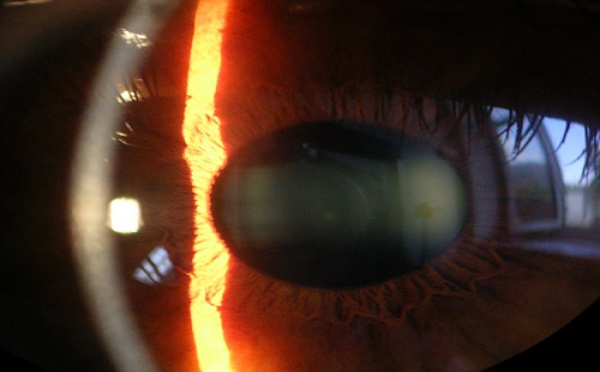

Un equipo de investigadores del Instituto de Óptica Daza de Valdés del CSIC ha desarrollado un método que permite obtener mapas cuantitativos de elevación de la córnea. Este sistema corrige la distorsión de barrido que afecta a la tomografía de coherencia óptica (conocida como OCT), capaz de obtener imágenes tridimensionales de esta parte del ojo.